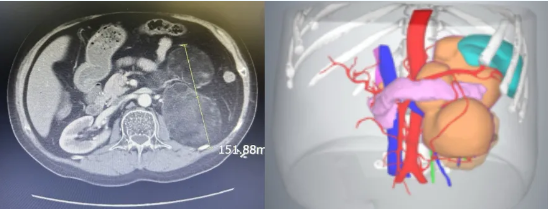

图片患者白某CT

患者白某4年前在自治区人民医院高血压科被确诊为17a-羟化酶缺陷症,并发现患有双侧肾上腺肿瘤,其中左侧肿瘤直径约17厘米且形态不规则,加之其血压不稳定,手术难度极大。面对如此复杂的病情和手术挑战,白某一度产生了放弃手术治疗的念头,陷入了深深的绝望之中。